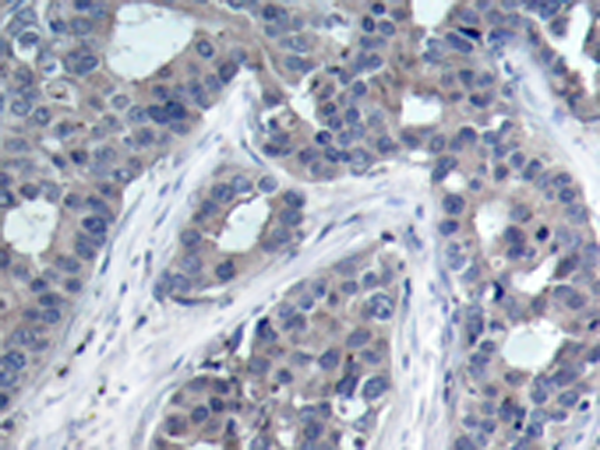

IHC positive control:

Human breast carcinoma